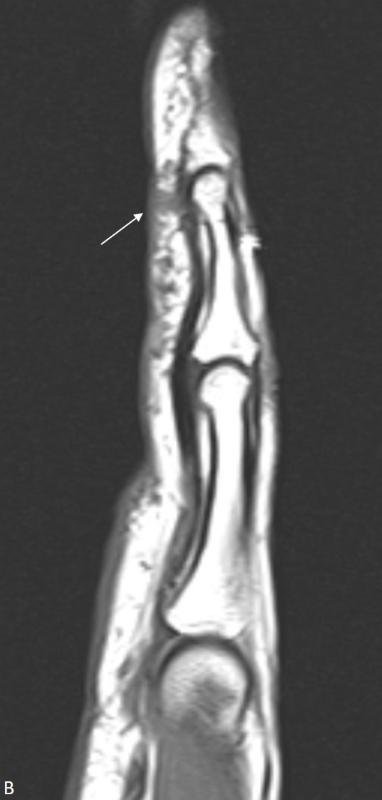

左手STIR序列冠位图像显示掌侧表皮下多个毫米、结节状的高信号强度病变,第4指指骨周围的病灶更大。

2212b132f57f8a60dd9c7f4a1305da10.jpgbe9dd1677b8ba2e94f3d512ce7329ad5.jpg